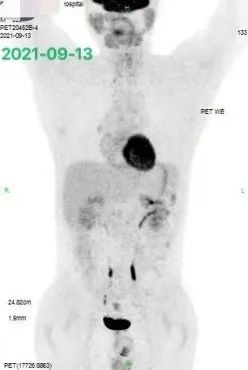

一周后患者体温及咳嗽,咳血明显改善,但仍然较为虚弱,我们避免了高强度的二线化疗,而给予了 1 疗程减量的 GDP 方案为主的化疗,并根据患者基因检测的结果选择了联合了 Bcl-2 抑制剂和阿扎胞苷。

化疗后患者症状进一步缓解,于是我们按期再次给予上述方案化疗 1 疗程。2 疗程化疗后的 CT 评估,证实我们对患者化疗敏感性的推断,病灶有了明显的缩小,如下图 4: